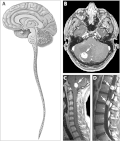

Hemangioblastoma is a low grade brain tumour tumour typically found the cerebellum.

• Usually cerebellar.

• occassionally brainstem or spinal cord. Supratentorial tumors are exceptionally rare.

Site brain - usu. cerebellum